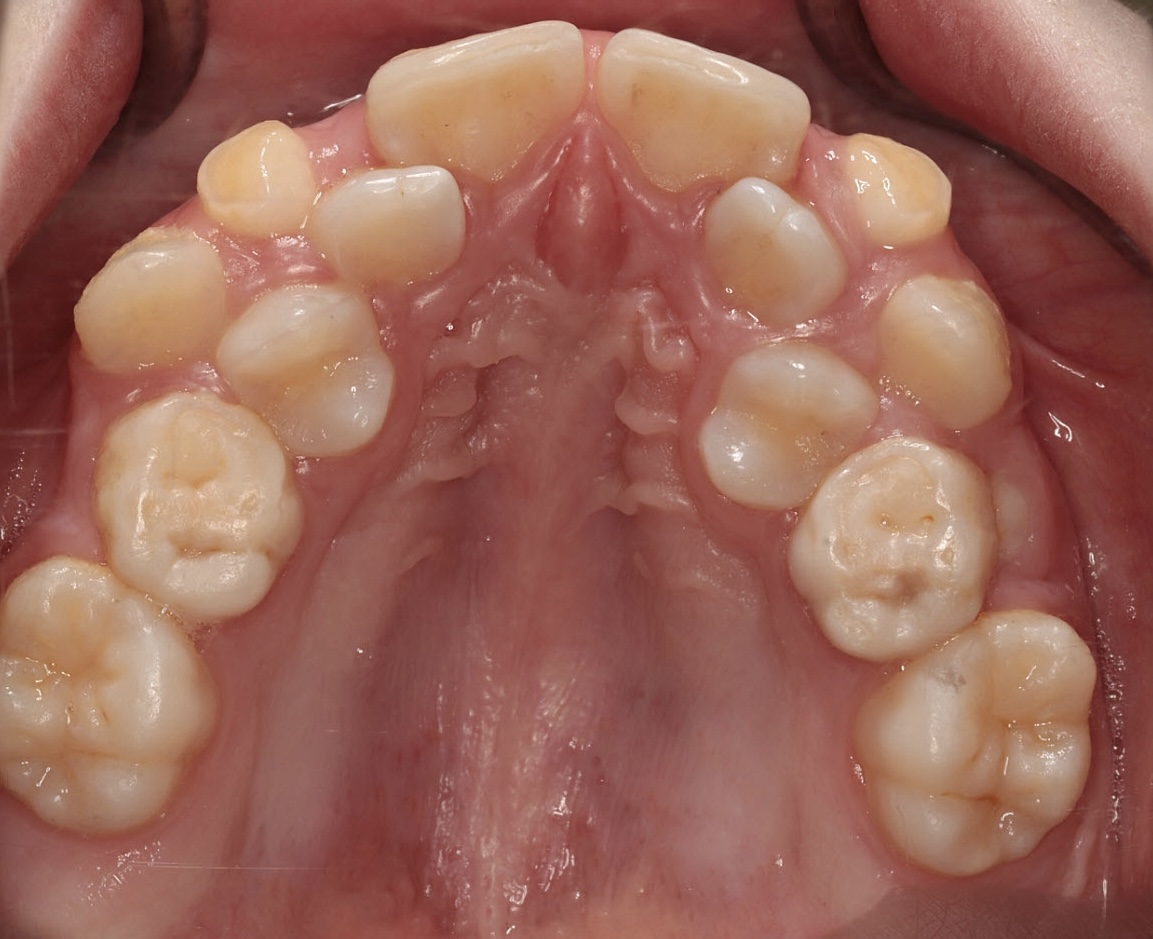

Will braces make my palate wider? Or should I keep mewing? Picture below

No palate expansion is needed. Shark teeth is a halo

God, you have worst teeth ever, you need braces and palate expander, talk to good ortho not the autists on this forum